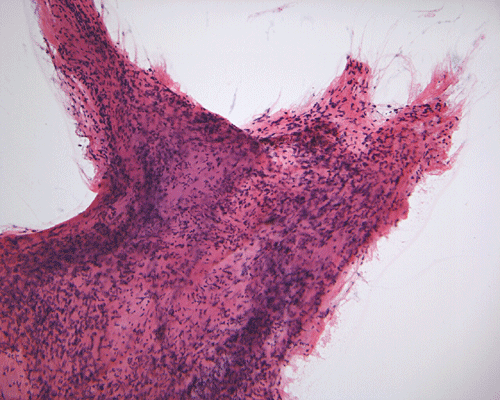

Pathology of the case: A small specimen was obtained by endoscopic biopsy. The specimen cannot be smear out after being squashed and remain as several, large, stellate-shaped cohesive clumps (Panel D). The edges of these clumps are relatively thin and allows better observations. The nuclei do not appear to be pleomorphic. Many elongated cytoplasmic processes can be seen (Panel E) and are suggest a glial nature of these cells. The lesion gives a spongy appearance on low-magnification (Panel F). On medium-magnification, there are some clustering of nuclei (Panel G). On high-magnification, the nuclei appear hyperchromatic and pointy but no substantial pleomorphism, prominent nucleoli, or mitotic figure. Some bluish, mucoid material is identified in some microcysts (Ú in Panel H).

There is no endothelial proliferation or necrosis. An  intraoperative diagnosis of glial neoplasm was made. The lesion was entirely resected. On paraffin section, the lesion has a hypocellular background decorated by many small microcysts, often in clusters, that contain mucoid material and small cluster of nuclei that resemble bundles of flowers (Panel I and J).  The nuclei are bland. There was no mitosis, endothelial proliferation or necrosis (Panel K and L).